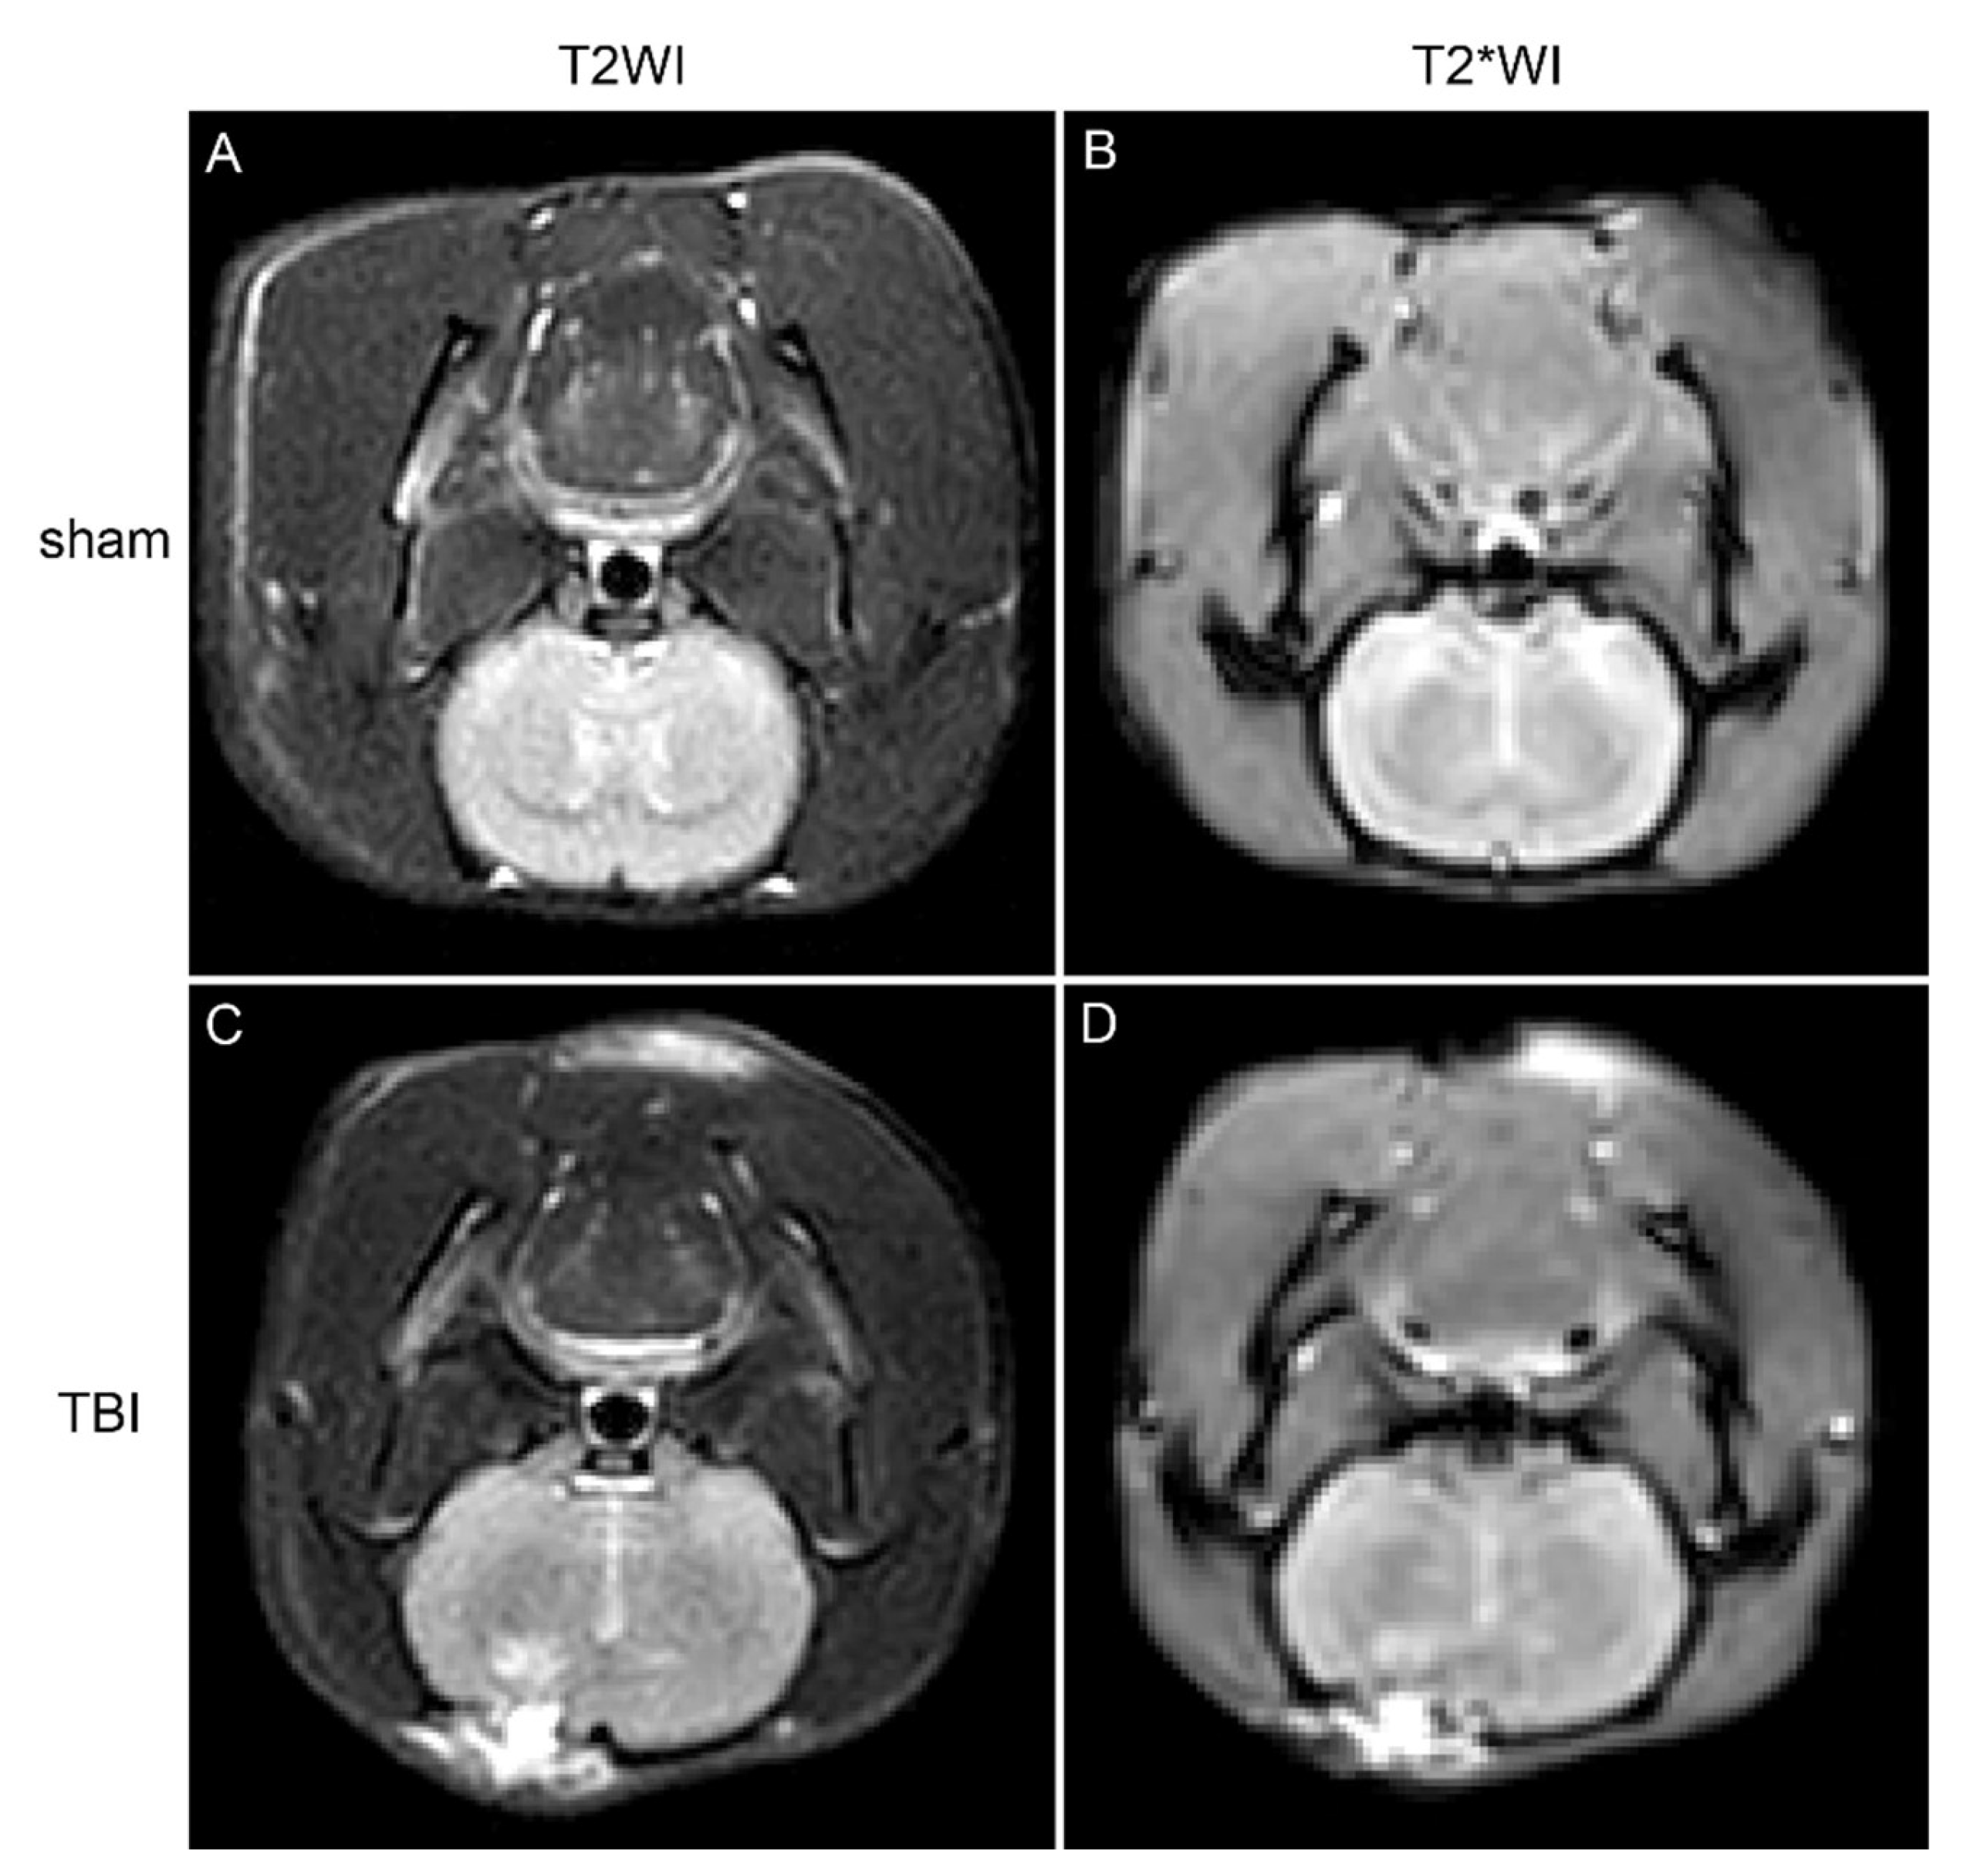

Seven days following the induction of TBI, magnetic resonance imaging (MRI) was conducted on the rats. In comparison to the sham group, the brain tissue within the injury region of the TBI cohorts exhibited elevated signal intensity on T2-weighted imaging (T2WI) sequences, indicative of brain injury, edema, and hemorrhagic events (Figure 1). Furthermore, diminished signal intensity was noted on T2*WI sequences surrounding the injury site, implying potential iron accumulation within the brain tissue (Figure 1).

Figure 1. Coronal MRI scans of rat brain tissue, with images A and B depicting the sham group (T2WI and T2WI sequences), and images C and D illustrating the TBI group (T2WI and T2WI sequences).

Our MRI findings demonstrated that TBI-induced brain tissue damage and iron deposition were apparent seven days post-injury. This observation was corroborated by transmission electron microscopy (TEM), which illustrated mitochondrial atrophy, membrane thickening, and rupture in neurons—hallmarks of ferroptosis. Prussian blue staining further validated that iron accumulation escalated with the severity of brain injury. These results underscore the significant role of ferroptosis in TBI-related neuronal damage and highlight the close association between iron deposition and the extent of injury.